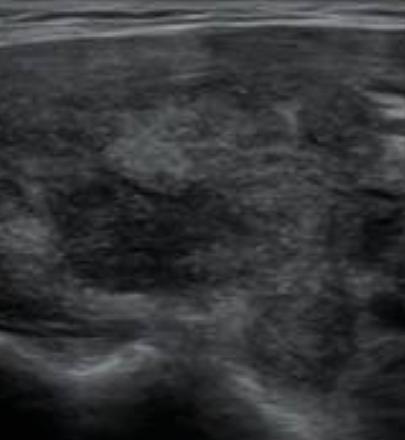

La característica más llamativa de esta prueba de imagen

que orienta a nuestro diagnóstico fue el aumento del tamaño de la glándula tiroides, con focos hipoecoicos dentro del parénquima normal (aspecto seudonodular con bordes mal definidos) y una disminución de la vascularización eco-Doppler (figuras 1 y 2).

Figura 1. Corte transversal del lóbulo tiroideo derecho. Se observan zonas hipoecogénicas con bordes mal definidos. Figura 2. Corte transversal del lóbulo tiroideo derecho. Se aprecia un aumento de tamaño de dicho lóbulo. Medida antero-posterior: 3,18 cm (valor normal 1-2 cm).